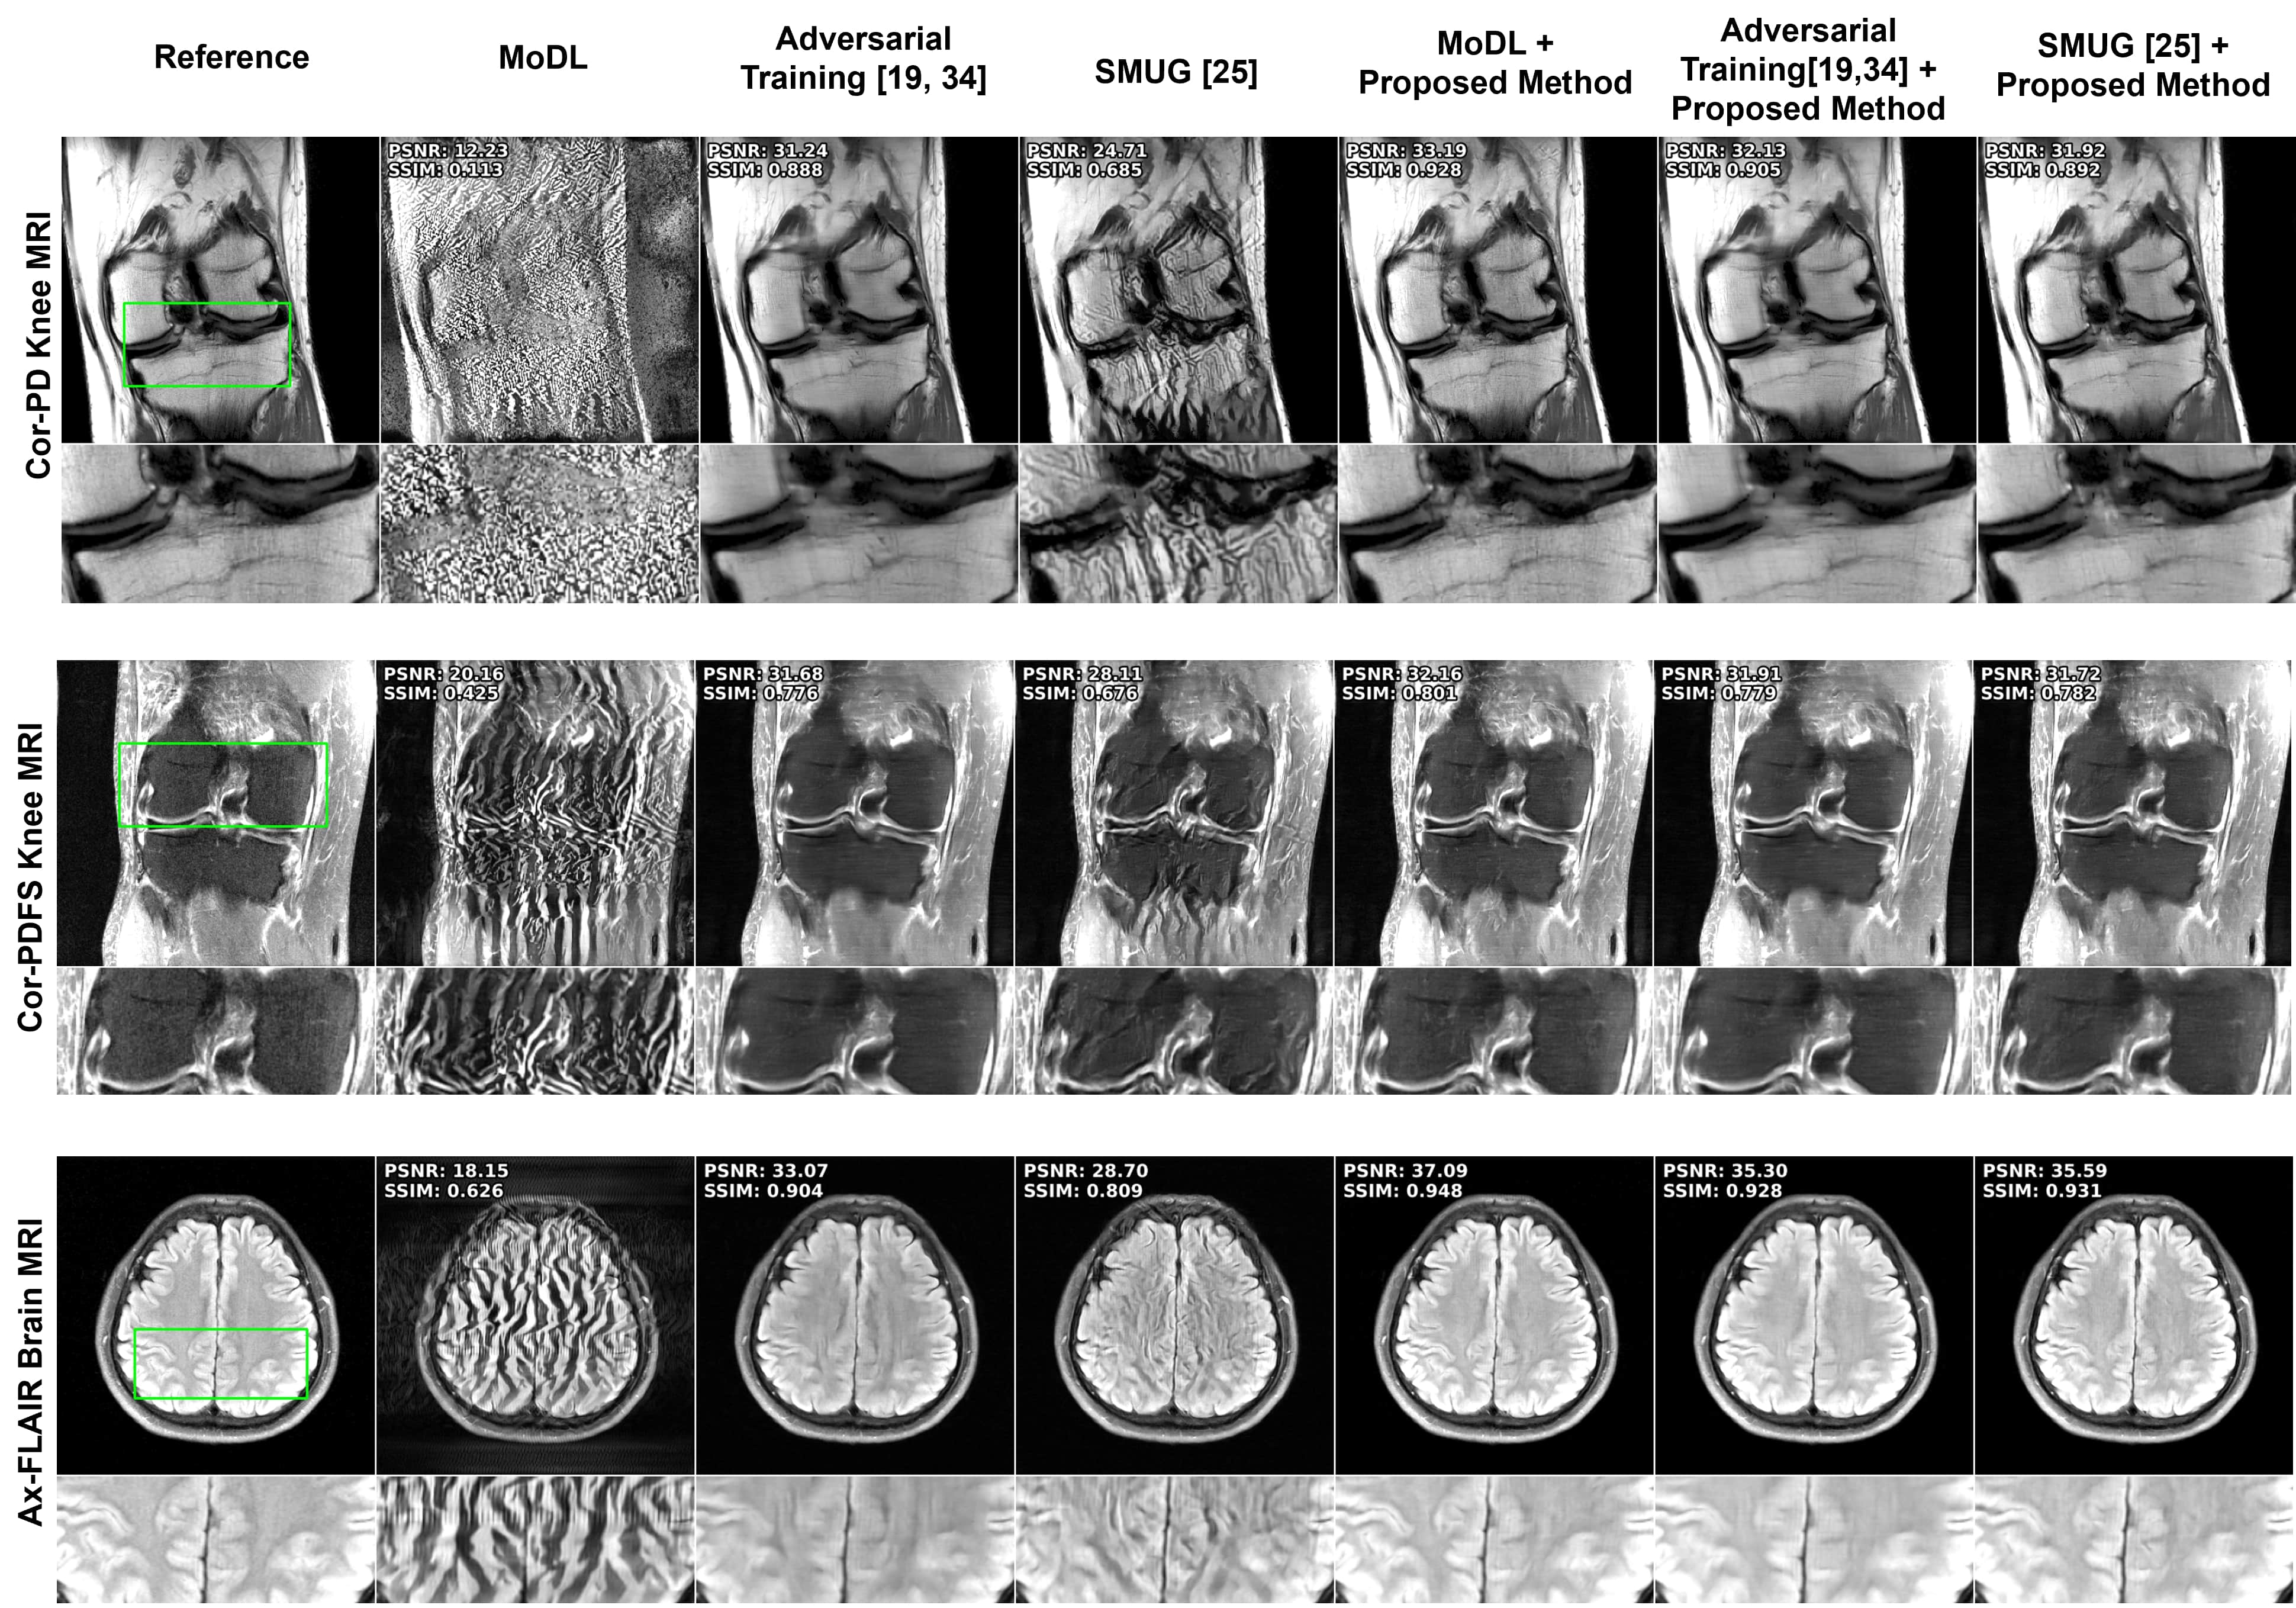

Refer to caption

Figure 3: Representative reconstruction results for Cor-PD knee, Cor-PDFS knee, and Ax-FLAIR brain MRI Datasets at R=4𝑅4R=4italic_R = 4. The attack inputs lead to severe disruption in the baseline MoDL reconstruction. Adversarial training improves these, albeit suffering from blurriness. SMUG fails to eliminate the attack. The proposed strategy reduces the artifacts and maintains sharpness. Furthermore it can be combined with the other strategies for further gains (last two columns).

Performance Across Datasets. We first investigate our approach and other comparison methods across the three different brain and knee MRI datasets. Fig 3 shows representative results for R=4𝑅4R=4italic_R = 4 for all methods. Baseline PD-DL, MoDL shows a high degree of artifacts under attack. SMUG is able to improve these but still suffers from substantial artifacts. Adversarial training resolves this artifacts, albeit with blurring. The proposed approach successfully mitigates the attacks without any retraining, while maintaining sharpness. We note our method can also be combined with SMUG and adversarial training to further improve their performance. Table 1 summarizes the quantitative metrics for all test slices in the datasets, which are consistent with the visual observations.